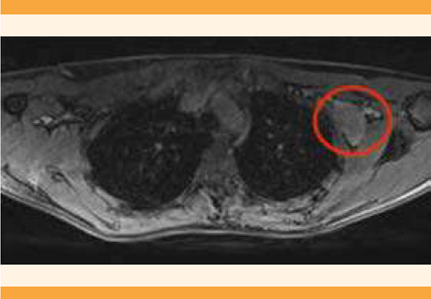

La resonancia magnética contrastada reportó nódulos sólidos bilaterales, sugerentes de fibroadenomas y adenopatías axilares en el lado izquierdo, que se clasificaron con BIRADS 4. Por lo anterior, se decidió la toma de una biopsia con aguja de corte de ganglio axilar izquierda, con reporte histopatológico de: proliferación linfoide atípica. La inmunohistoquímica reportó positividad en: CD20, CD3, CD21 en células dendríticas interfoliculares, Ki-67 y negatividad para HHV-8 en centros germinales residuales. Figura 3

Figura 3 Nivel 1 de la región axilar izquierda. Se observa una adenopatía con importante realce, posterior a la administración de gadolinio.